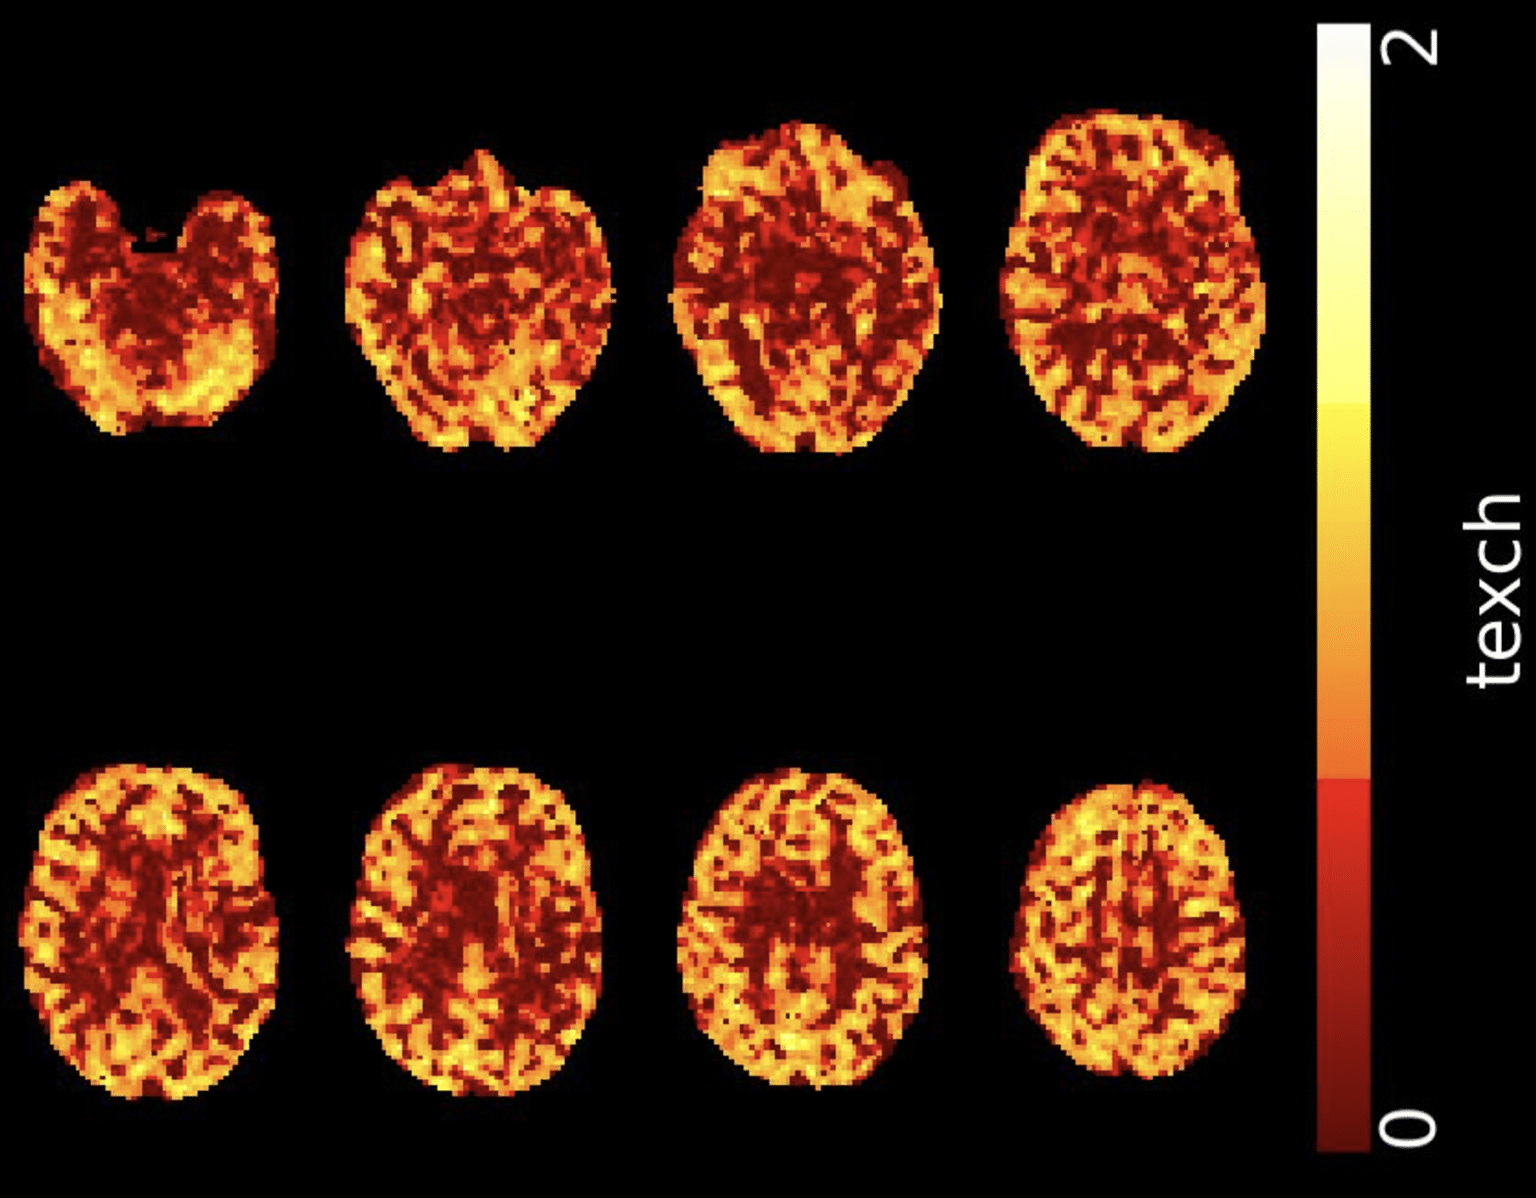

Texch image of BBB integrity for a healthy subject, acquired using multi-echo ASL on a Siemens 3T.